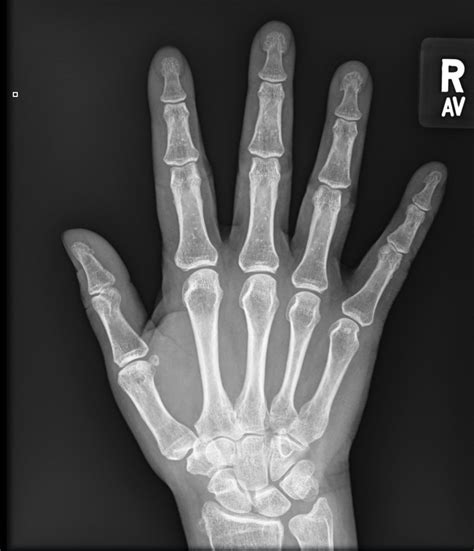

Normal X-Ray Of Right Hand . Normal ap view of the right hand in an adult patient. Web the radiographs of the right hand in the ap (a), lateral (b), and oblique (c) projections are normal.

Normal oblique view of the right hand. Symmetrical joints where the bones do not overlap (except the carpal bones and the base of the. Web the radiographs of the right hand in the ap (a), lateral (b), and oblique (c) projections are normal.